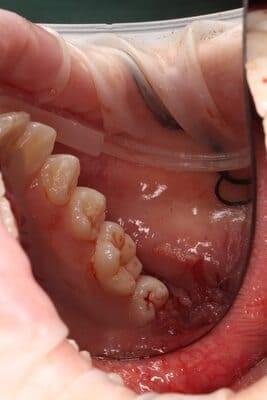

Один рік і два місяці вік дитини. Хтось скаже: «Що там тим зубам можна лікувати?!» Однак є ситуації, коли каріозний процес розвивається просто блискавично. Часто це пов’язано з порушеннями у формуванні твердих тканин ще внутрішньоутробно. А коли такі зубчики прорізуються, руйнування відбувається просто «на очах». Вісім із восьми зубів уражені, а 4 з них потребують часткового видалення пульпи («нерва»). На цьому етапі зуби вже починають турбувати і не зважаючи на юний вік дитини, зволікати не можна. Завдяки високій компетенції наших анестезіологів, які працюють з дітьми від самого народження і навіть з передчасно народженими, ми можемо проводити відповідне лікування в анестезіологічному забезпеченні за потреби навіть з першого зуба. Верхнім зубчикам, які сильно уражені, служити до 7-8 років, тому вони покриваються стандартними естетичними цирконієвими коронками, які дають максимальний результат по надійності, функції та естетиці. Година з половиною роботи і дитина може знову кусати без болю і дискомфорту. Важливо пам’ятати: для лікування зубів ніколи не буває “зарано”, це потрібно робити тоді, коли є відповідні показання